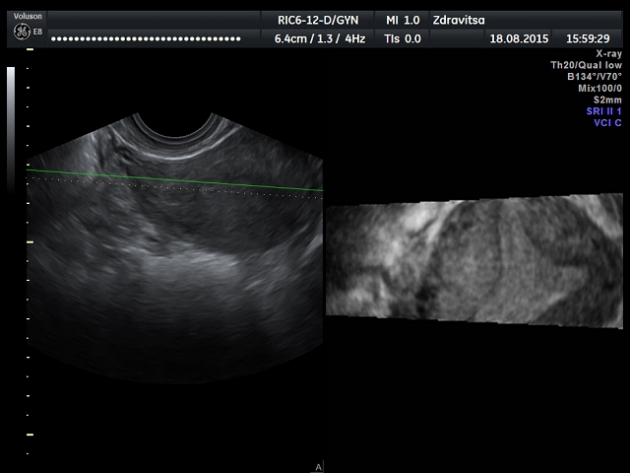

Случай №1. Молодая девушка обратилась для проведения УЗИ почек, при проведении которого обнаружено полное удвоение левой почки. Заглянула в малый таз, увидела следующее: